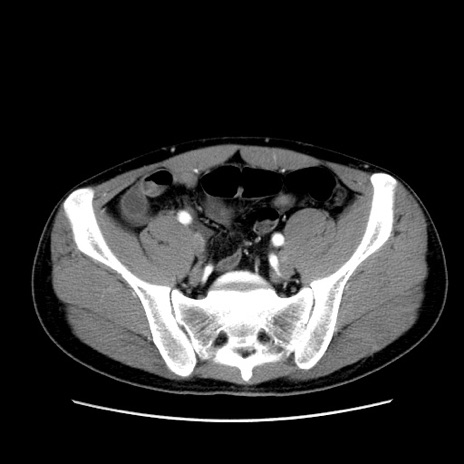

症例36(横断像)

【症例】20歳代 男性

【主訴】心窩部痛

【現病歴】今朝より上腹部痛あり。一旦軽快していたが再度出現したため救急要請。昨日夕に白身の魚を含む刺身を食べた。

【身体所見】BP 136/89mmHg、HR 74/min、BT 37.0℃、腹部:膨満、軟、心窩部に圧痛あり。反跳痛なし、筋性防御なし、腸雑音やや亢進あり。

【データ】WBC 17700、CRP 0.48